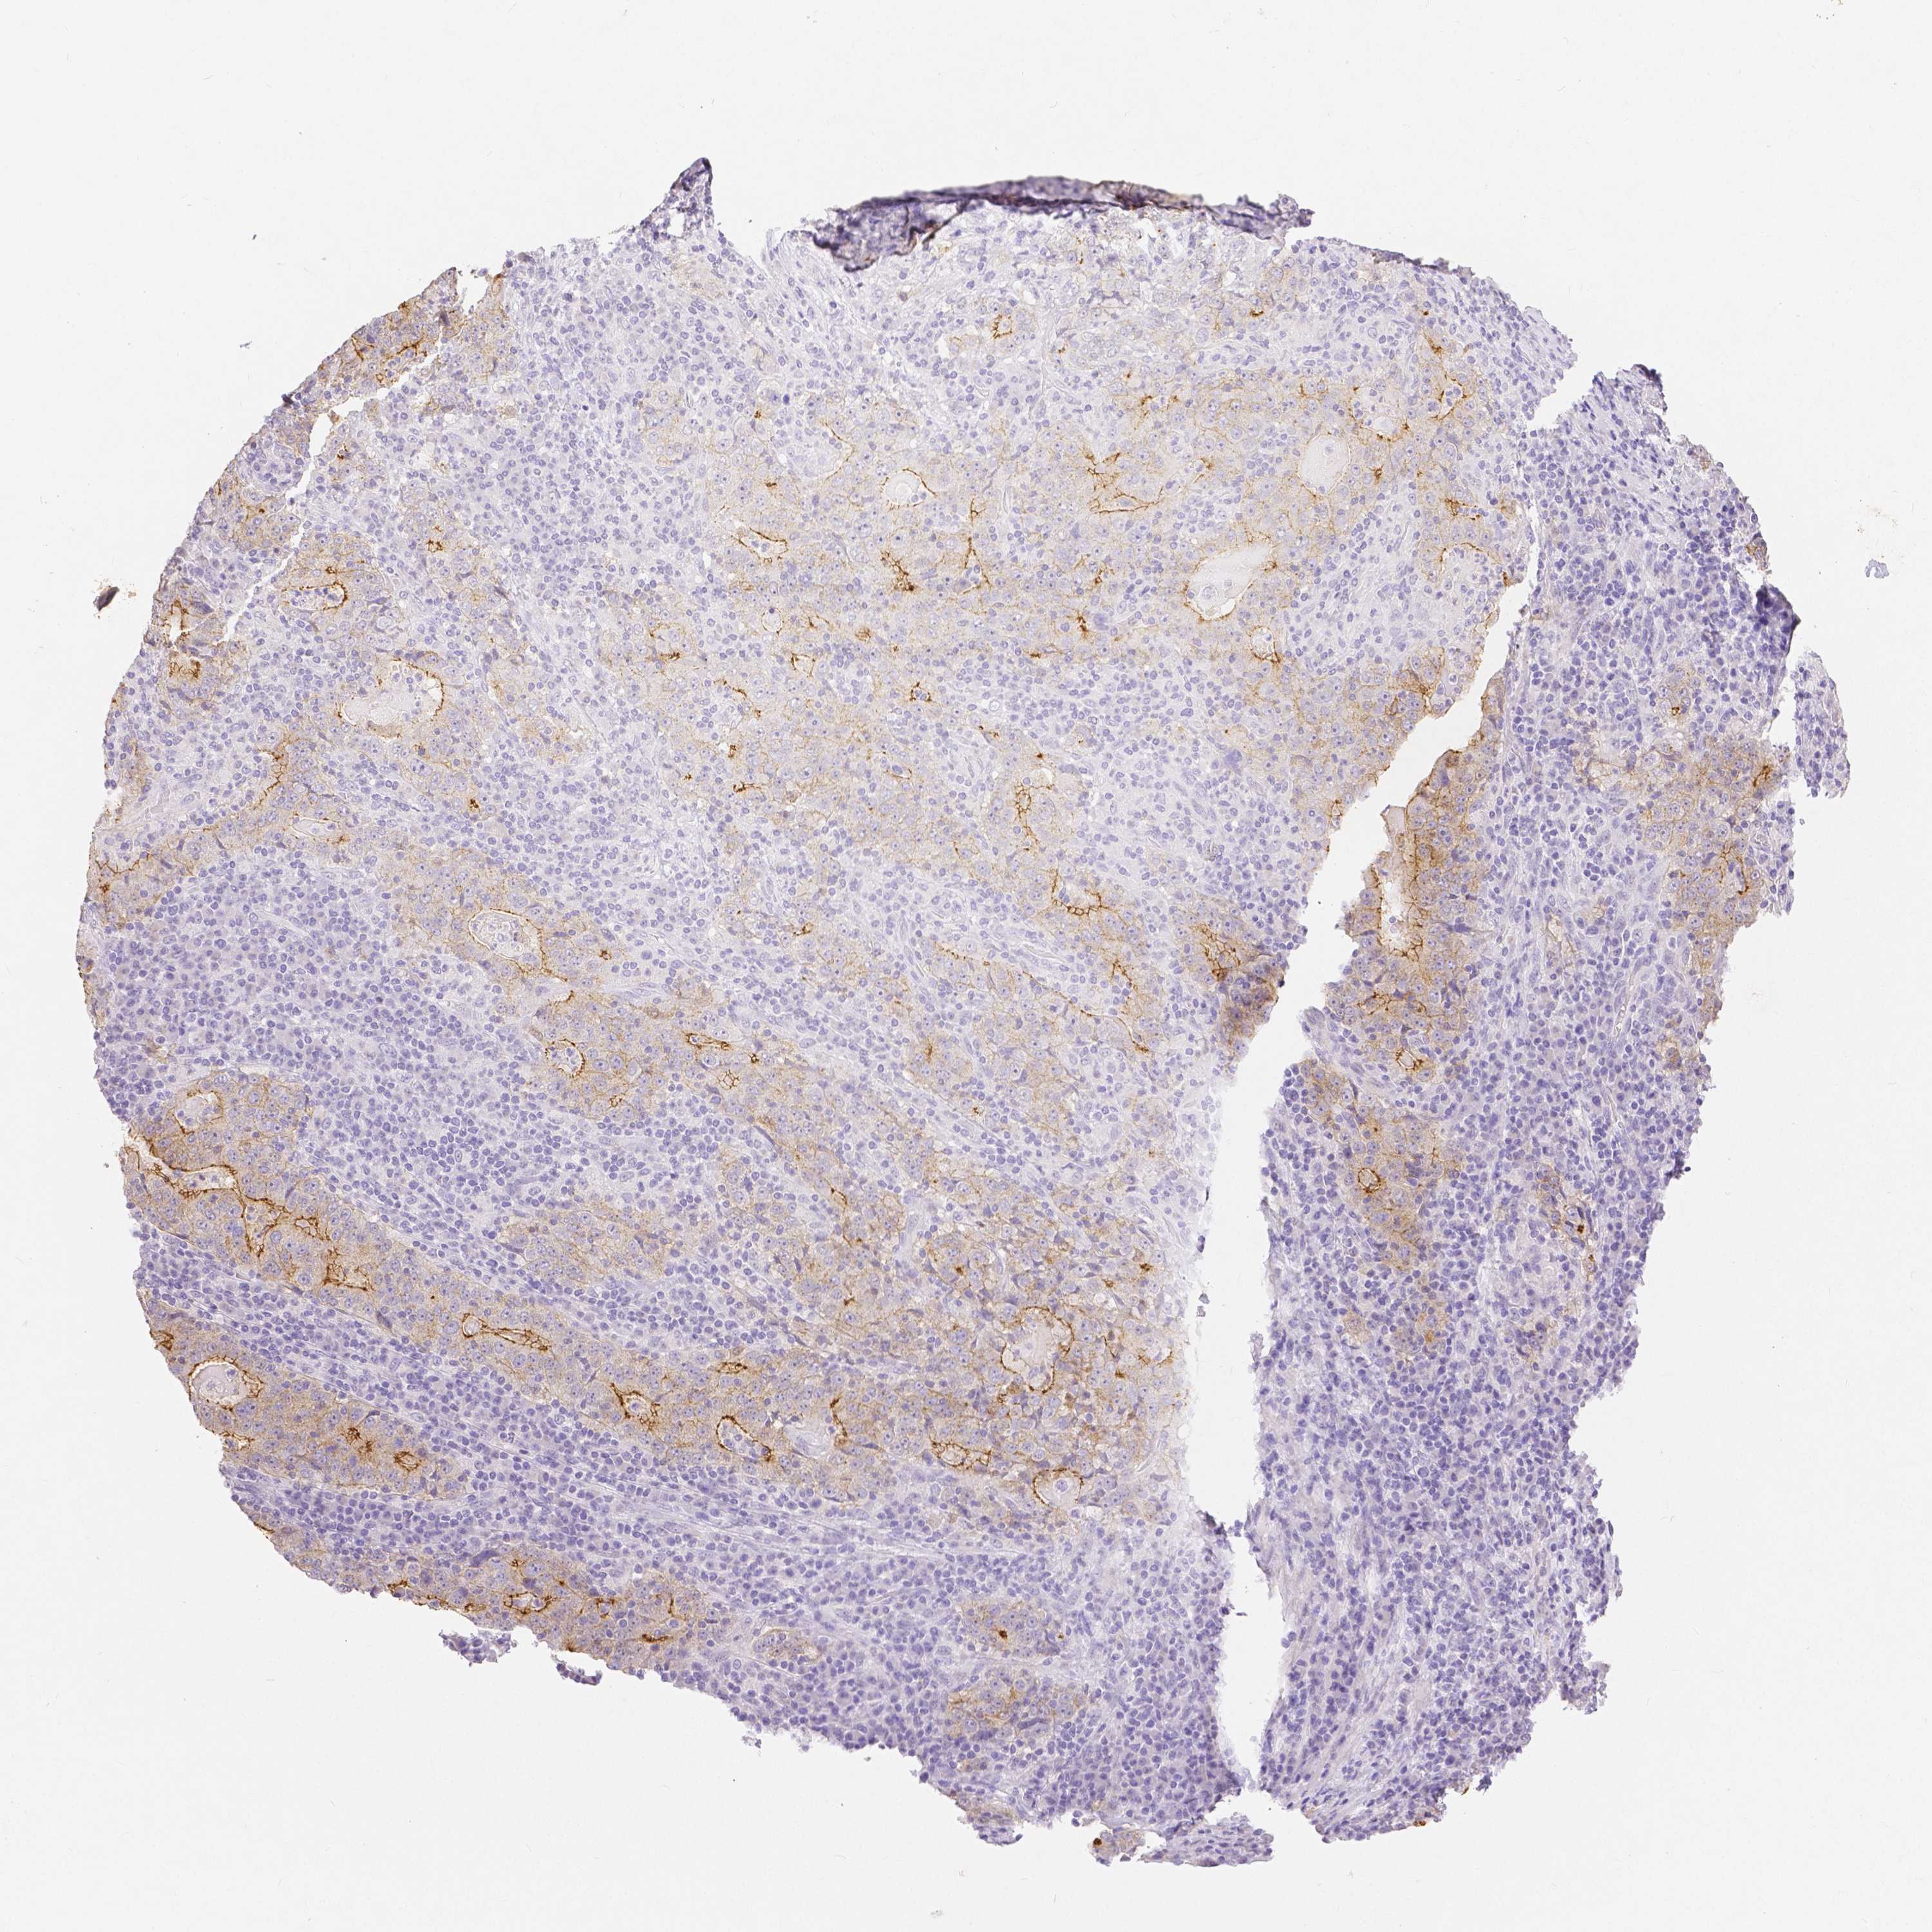

STOMACH CANCER - Protein expressioni

A mouse-over function shows sample information and annotation data. Click on an image to view it in a full screen mode. Samples can be filtered based on level of antibody staining by selecting one or several of the following categories: high, medium, low and not detected. The assay and annotation is described here.

Note that samples used for immunohistochemistry by the Human Protein Atlas do not correspond to samples in the TCGA dataset.

Antibody stainingi

Antibody staining in the annotated cell types in the current human tissue is reported as not detected, low, medium, or high, based on conventional immunohistochemistry profiling in selected tissues. This score is based on the combination of the staining intensity and fraction of stained cells.

Each image is clickable and will lead to virtual microscopy that enables deeper exploration of all samples and also displays staining intensity scores, fraction scores and subcellular localization as well as patient and tissue information for each sample.

HPA005933

CAB013075

CAB068212

CAB068213

CAB068214

Adenocarcinoma, NOS

Adenocarcinoma, High grade